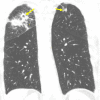

Pulmonary embolism (PE) is a serious condition that often poses a diagnostic challenge. We report a case of a 57-year-old man with tobacco dependence who presented with multiple trauma, with chest imaging findings concerning for malignancy. While performing bronchoscopy with endobronchial ultrasound (EBUS), an echogenic material was incidentally found in the left pulmonary artery. Computed tomography pulmonary angiography (CTPA) was immediately obtained and confirmed the diagnosis of PE. This case illustrates the utility of routine pulmonary artery examination during EBUS procedures in patients at risk of PE and the importance of prompt management including confirmation with CTPA.